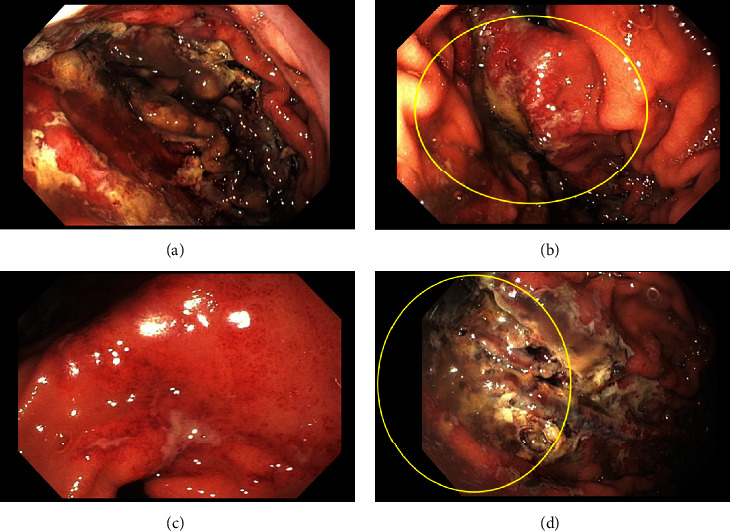

我们报告了一个病例,一名 62 岁的男子因摔倒和精神状态改变而被紧急医疗服务人员送来。他被发现患有严重的高钾血症、急性肾损伤和横纹肌溶解症。高钾血症用聚苯乙烯磺酸钠(SPS)治疗。住院期间,他目睹了黑色柏油样粪便和血红蛋白的显著下降。内镜检查显示,他的胃部有不出血的大面积弥漫性溃疡,并有近期出血的痕迹,溃疡活检结果显示与 SPS 引起的胃溃疡一致。局部没有发现其他出血源,这表明急性上消化道出血是由 SPS 粘膜损伤引起的。

We report a case of a 62-year-old man who was brought in by emergency medical services after a fall and change in mental status. He was found to have severe hyperkalemia, acute kidney injury, and rhabdomyolysis. The hyperkalemia was treated with sodium polystyrene sulfonate (SPS). During hospitalization, he witnessed having black tarry stools along with a significant drop in hemoglobin. Endoscopic evaluation demonstrated nonbleeding large diffuse gastric ulcers with stigmata of recent bleeding, and ulcer biopsy revealed findings consistent with SPS-induced gastric ulceration. No other source of bleeding was localized, suggesting acute upper gastrointestinal bleeding due to SPS mucosal injury.